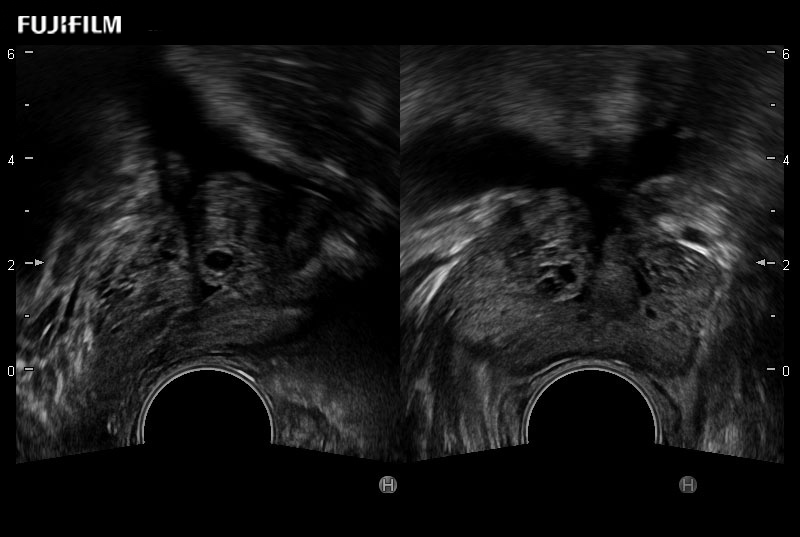

Exclusive 200° FOV end-fire prostate biopsy transducer.

Provides real-time imaging of both the sagittal and transverse planes